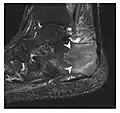

Fatigue fractures are more frequent in women which may be due to the relatively smaller bones of women. Moreover, pregnancy is a well-recognized risk factor for femoral neck fatigue fracture. While fibular and metatarsal fractures have a low risk of complications, other sites including the femoral neck, midanterior tibia, navicular, talar, and other intraarticular fractures are prone to complications such as delayed union, nonunion, and displacement. The site of the insufficiency fracture may be specific to the activity: for example, rugby and basketball players are more prone to navicular fractures, while gymnasts have a higher risk for talar fractures (Figure 7). Long distance runners are at increased risk for pelvic, tibial (Figures 8 and 9), and fibular fractures. In the military, calcaneus (Figure 10) and metatarsals are the most commonly cited injuries, especially in new recruits. Billiard players are at risk for upper limb fractures (Figure 11).[1]

-

a -

b

Figure 7: Fatigue fracture of the talus in a 25-year-old male basketball player with right hind foot and ankle pain, without history of trauma, and a normal initial radiograph (not shown). (a) One-month followup lateral radiograph shows normal appearance. (b) Sagittal T1-weighted MRI shows an irregular fracture line (arrow) within an ill-defined area of hypointensity corresponding to bone marrow edema.[1]